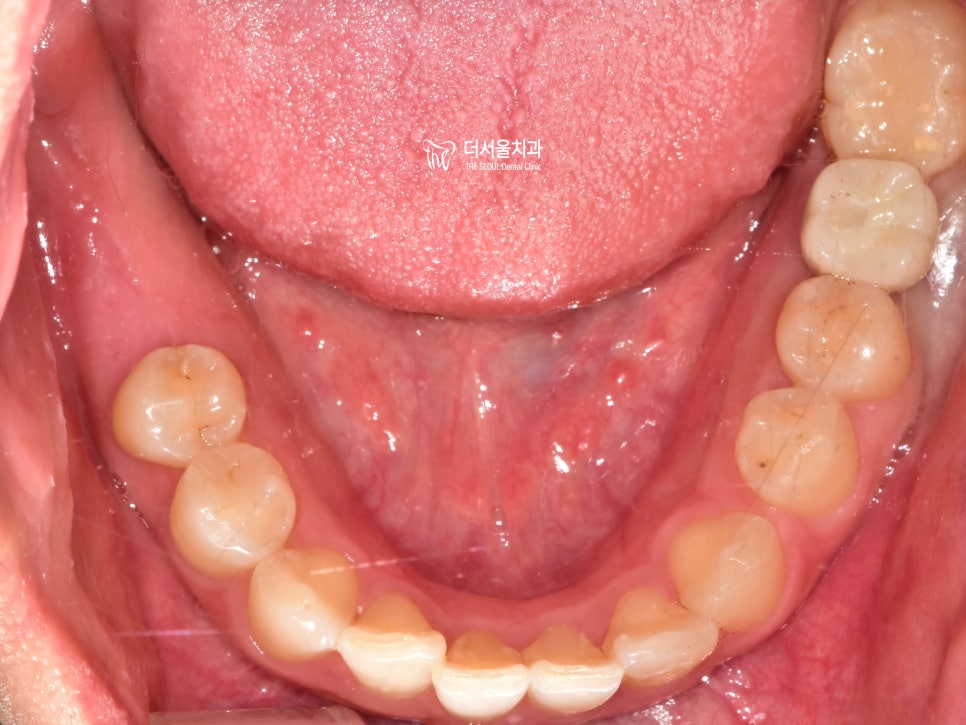

우선 남아있는 곳들을

깨끗하게 제거해주었습니다.

잇몸이 회복될 때까지 어느정도 기간을 부여한 뒤,

좌측과 마찬가지로 컴퓨터 분석을 통해

식립 위치 및 방향, 각도 등을 결정했습니다.